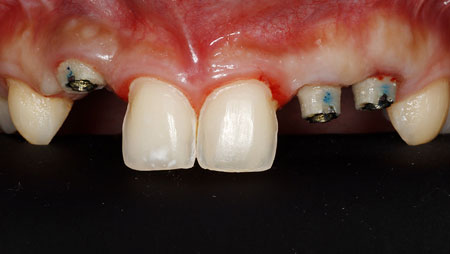

Keys for Successful Aesthetic Zone Single Implant: Case Reports

Noroozi_3Fig5 alternate text for this image

To achieve a successful aesthetic result and good patient satisfaction, implant placement in the aesthetic zone demands a thorough understanding of anatomic, biologic, surgical and prosthetic principles. The ability to achieve harmonious, indistinguishable restoration from adjacent natural teeth in the aesthetic zone is very often challenging. Placement of dental implants in the aesthetic zone is … Read more